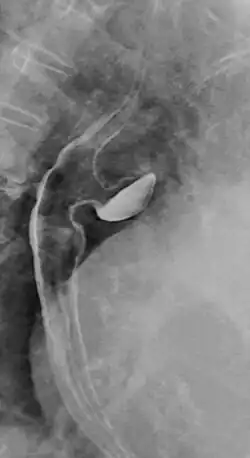

Ösophagusdivertikel

Das Ösophagusdivertikel und der Ösophaguspouch sind Ausstülpungen bzw. Erweiterungen (Divertikel) der Speiseröhre, die sich in unterschiedlichen Höhen derselben finden, unterschiedliche Ursachen und einen unterschiedlichen Krankheitswert haben. Man unterscheidet

- Zervikale ösophageale Pouches